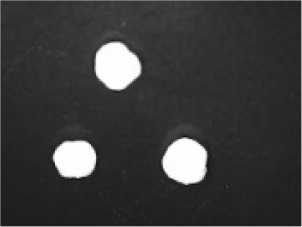

In addition to the disintegration endpoint studied using the USP disintegration apparatus, the pellets disintegrated into particles of various sizes when evaluated at a static position. A few drops of water were placed on the pellets on the opaque surface. A USB digital microscope (China) was connected to a computer to capture the disintegration process. Images were captured from the beginning until the pellet disintegrated or exploded into small fragments. Pellet images were acquired every 30 seconds. for formulations containing polyplasdone XL 10 and croscarmellose sodium.

Disintegration was evaluated at room temperature under static conditions. The camera captured images every 30 s ( Table 9), illustrating that MCC pellet X3 with mannitol and PEG 400 did not disintegrate. Within 120 s, cracks appeared in P5 pellets containing mannitol, PEG, and PPXL. As seen in the C4 pellets, they begin to explode into many fragments within 30 s. Moreover, the CP12 pellets containing PEG 400, mannitol, CCS, and PPXL began to explode into many loosely linked particles after 60 s, which quickly separated under the oscillating motion of the USP disintegration equipment. The photographs are compatible with the results mentioned above for the USP disintegration device. When the temperature was increased to 37°C, the disintegration caused the split into tiny fragments.

Table 9. Camera capture of pellet disintegration at different time intervals.

Pellet # 0 sec. 30 sec. 60 sec. 90 sec. 120 sec.

X3c9c3975f-9288-4951-a800-a8e9fc463382_GRA58.gif c9c3975f-9288-4951-a800-a8e9fc463382_GRA59.gif c9c3975f-9288-4951-a800-a8e9fc463382_GRA60.gif c9c3975f-9288-4951-a800-a8e9fc463382_GRA61.gif c9c3975f-9288-4951-a800-a8e9fc463382_GRA62.gif

P5c9c3975f-9288-4951-a800-a8e9fc463382_GRA63.gif c9c3975f-9288-4951-a800-a8e9fc463382_GRA64.gif c9c3975f-9288-4951-a800-a8e9fc463382_GRA65.gif c9c3975f-9288-4951-a800-a8e9fc463382_GRA66.gif c9c3975f-9288-4951-a800-a8e9fc463382_GRA67.gif

C4c9c3975f-9288-4951-a800-a8e9fc463382_GRA68.gif c9c3975f-9288-4951-a800-a8e9fc463382_GRA69.gif c9c3975f-9288-4951-a800-a8e9fc463382_GRA70.gif c9c3975f-9288-4951-a800-a8e9fc463382_GRA71.gif c9c3975f-9288-4951-a800-a8e9fc463382_GRA72.gif

CP12c9c3975f-9288-4951-a800-a8e9fc463382_GRA73.gif c9c3975f-9288-4951-a800-a8e9fc463382_GRA74.gif c9c3975f-9288-4951-a800-a8e9fc463382_GRA75.gif c9c3975f-9288-4951-a800-a8e9fc463382_GRA76.gif c9c3975f-9288-4951-a800-a8e9fc463382_GRA77.gif

CPP4c9c3975f-9288-4951-a800-a8e9fc463382_GRA78.gif c9c3975f-9288-4951-a800-a8e9fc463382_GRA79.gif c9c3975f-9288-4951-a800-a8e9fc463382_GRA80.gif c9c3975f-9288-4951-a800-a8e9fc463382_GRA81.gif c9c3975f-9288-4951-a800-a8e9fc463382_GRA82.gif

CPO4c9c3975f-9288-4951-a800-a8e9fc463382_GRA83.gif c9c3975f-9288-4951-a800-a8e9fc463382_GRA84.gif c9c3975f-9288-4951-a800-a8e9fc463382_GRA85.gif c9c3975f-9288-4951-a800-a8e9fc463382_GRA86.gif c9c3975f-9288-4951-a800-a8e9fc463382_GRA87.gif

The CP12 pellet disintegration process is depicted in the video in the supplementary material (refer to underlying data). The pellets swelled immediately before exploding and quickly disintegrating. The orphenadrine citrate pellets began to swell and cracks appeared after 120 s, which were easily separated under the oscillating motion of the USP disintegration equipment. The photographs are compatible with the results of the USP disintegration device. When the temperature was increased to 37°C, disintegration caused the fragments to split into smaller fragments. When the temperature was increased to 37°C, disintegration caused the split into tiny fragments. The pseudoephedrine hydrochloride pellets began to explode into several pieces of loosely linked particles within 120 s, which were easily separated by the oscillating motion of the USP disintegration equipment. The photographs were compatible with the results obtained from the USP disintegration device. When the temperature increased to 37°C, the disintegration caused the split into tiny fragments. Although this is not an official USP test, using video capture for disintegration validates Chamsai’s claim of quick disintegration.18